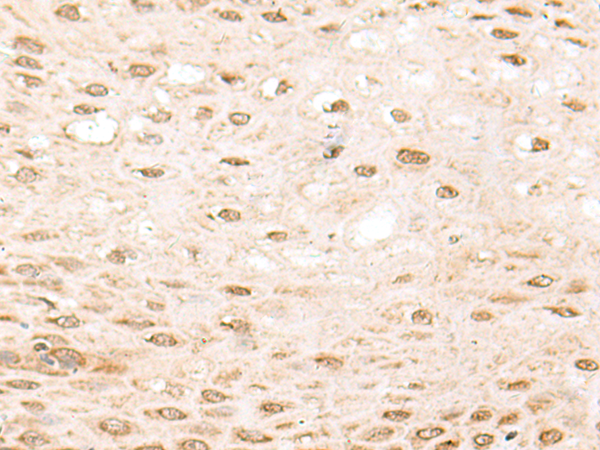

分类: 科研抗体货号: P04437别名: 42A, 18A2, CAPL, FSP1, MTS1, P9KA, PEL98应用: IHC反应种属: Human